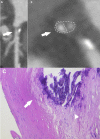

SARS-CoV-2 infection, responsible for COVID-19 outbreak, can cause cardiac complications, worsening outcome and prognosis. In particular, it can exacerbate any underlying cardiovascular condition, leading to atherosclerosis and increased plaque vulnerability, which may cause acute coronary syndrome. We review current knowledge on the mechanisms by which SARS-CoV-2 can trigger endothelial/myocardial damage and cause plaque formation, instability and deterioration. The aim of this review is to evaluate current non-invasive diagnostic techniques for coronary arteries evaluation in COVID-19 patients, such as coronary CT angiography and atherosclerotic plaque imaging, and their clinical implications. We also discuss the role of artificial intelligence, deep learning and radiomics in the context of coronary imaging in COVID-19 patients.